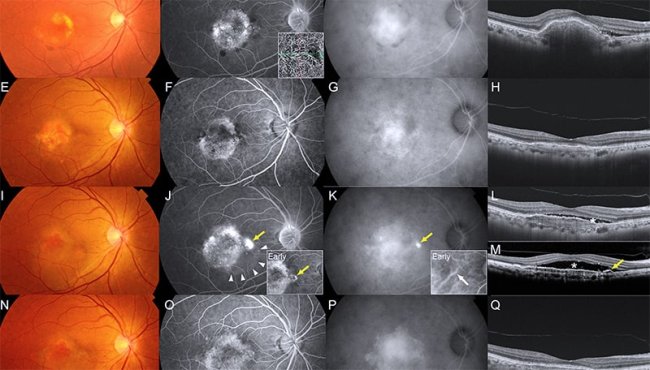

Диагностика ЦСХ основана на сочетании жалоб и данных инструментальных исследований. Проводят проверку остроты зрения, офтальмоскопию, оптическую когерентную томографию (ОКТ), позволяющую визуализировать серозную отслойку нейроэпителия и оценить толщину макулы. Важную роль играет флуоресцентная ангиография, с помощью которой выявляют точку утечки (leakage) и дефекты пигментного эпителия.